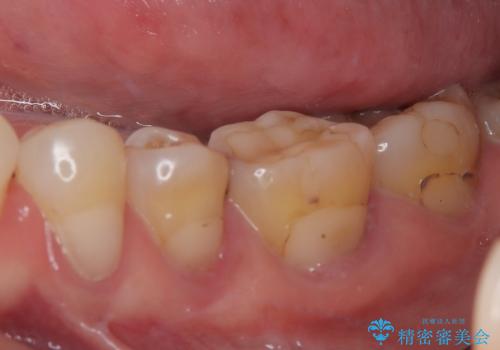

- 奥歯の間にものが挟まって不快であるとのことで来院された患者様です。

検査を行った結果、非常に強い咬合力により隣の歯との隣接面にひびが入り、虫歯が拡大している状態でした。

部分的にゴールドインレーが装着されていたので、虫歯と合わせて除去し、新たにゴールドインレーにて修復治療を行うこととしました。